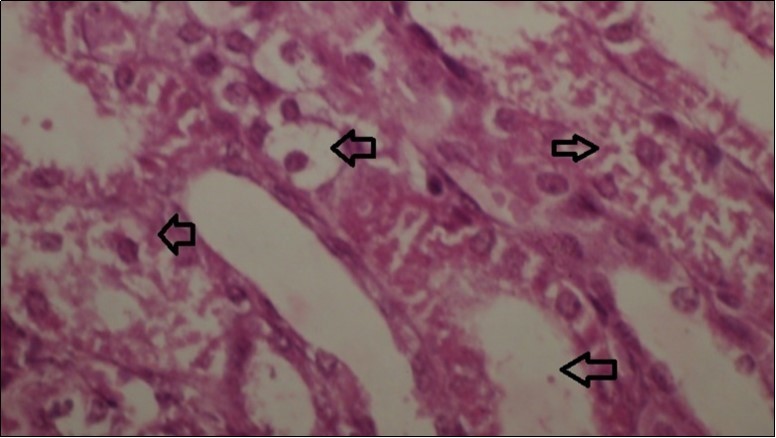

Figures 6.kidneys (dead cattle less than 1 year old) showed severe hydropic degeneration of renal tubular epithelium accompanied by dilated renal tubules, vesicles formations and casts (arrows). (H&E, X 100)

Figures 7.kidneys (dead cattle less than 1 year old) showed severe hydropic degeneration of renal tubular epithelium accompanied by dilated renal tubules, vesicles formations and casts (arrows). (H&E, X 60)